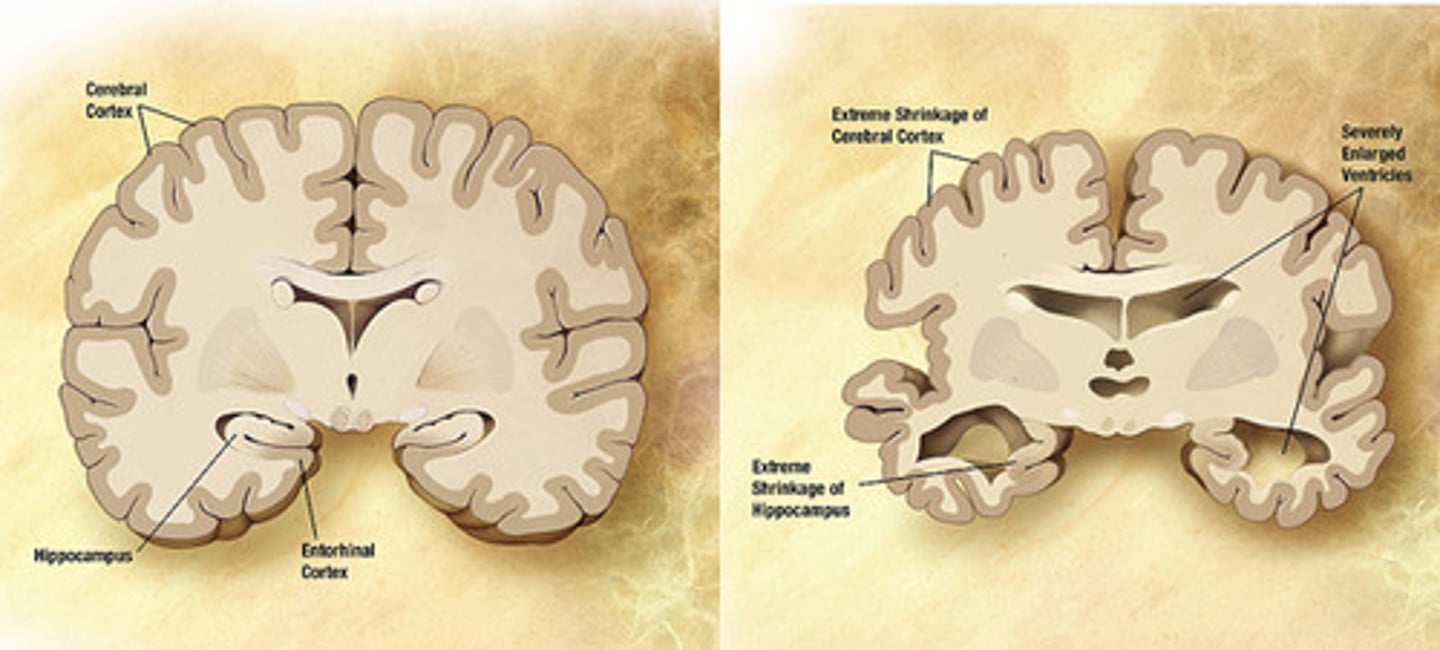

MMSE score of less than ___ is suggestive of dementia (total maximum is 30).

24 points

- Neuro imaging shows atrophy which is more prominent in the temporal and parietal lobes

Risk factors for Alzheimers dementia.

Age

Female gender

Positive family history

Head trauma

Down's syndrome

Normal pressure hydrocephalus

Ataxia early in the disease

Urinary incontinence

Dilated ventricles on neuroimaging